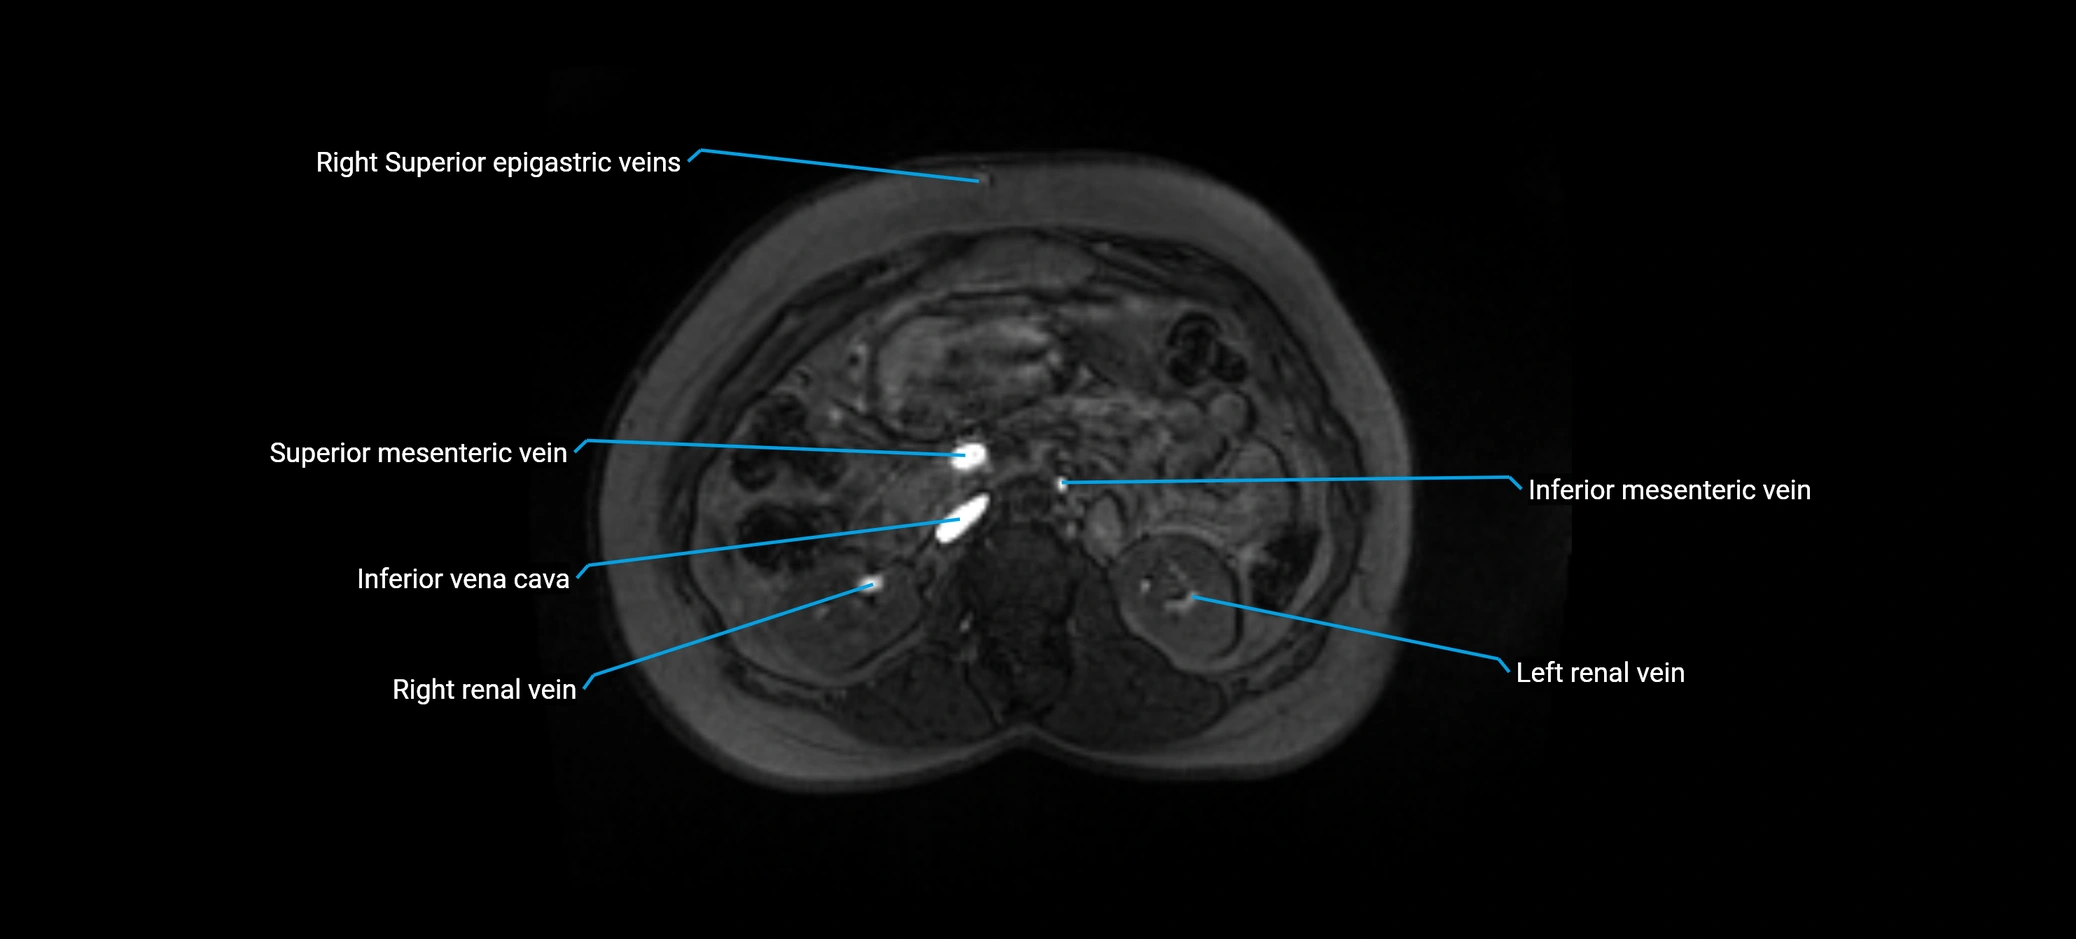

MRI image

image